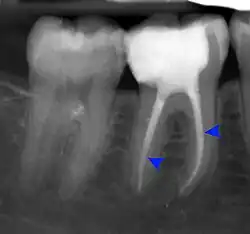

- Radiographs utilized to find dental caries and bone loss laterally or at the apex.

Decay (green) with apical abscess (blue) -

Gutta-percha point indicating abscess origin